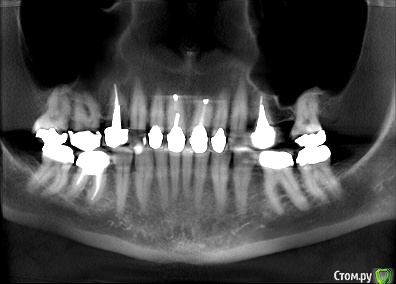

togrul Опубликовано 17 марта, 2015 Автор Поделиться Опубликовано 17 марта, 2015 взят из КТ Ссылка на комментарий

Rash163 Опубликовано 17 марта, 2015 Поделиться Опубликовано 17 марта, 2015 Я промерил бы глубину карманов.что там как. По снимку не очень видно. Определился с размерами фронтальных зубов, воск или дсд. 11,21 кажется висят относительно других.после этого будет понятно что делать. Пломбу на 11 убрать бы, десне очень плохо около нее. Ссылка на комментарий

Skip Опубликовано 17 марта, 2015 Поделиться Опубликовано 17 марта, 2015 есть модели загипсованные в ЦС. Вот это самое интересное. Особенно, учитывая удалённые премоляры. Ссылка на комментарий

krokomot Опубликовано 17 марта, 2015 Поделиться Опубликовано 17 марта, 2015 Добрый день коллеги. Обратилась пациентка с просьбой заменить все реставрации + привести эстетически все в порядок.С чего бы вы начали? есть модели загипсованные в ЦС. Снимок КТ.Маловато информации, что с высотой прикуса?, Какова зона улыбки и в спокойном состоянии, пациентка расчитывает только на протезирование или с пластикой десны?, сроки? бюджет? и где ваши модели в цс? все размыто, извините Ссылка на комментарий